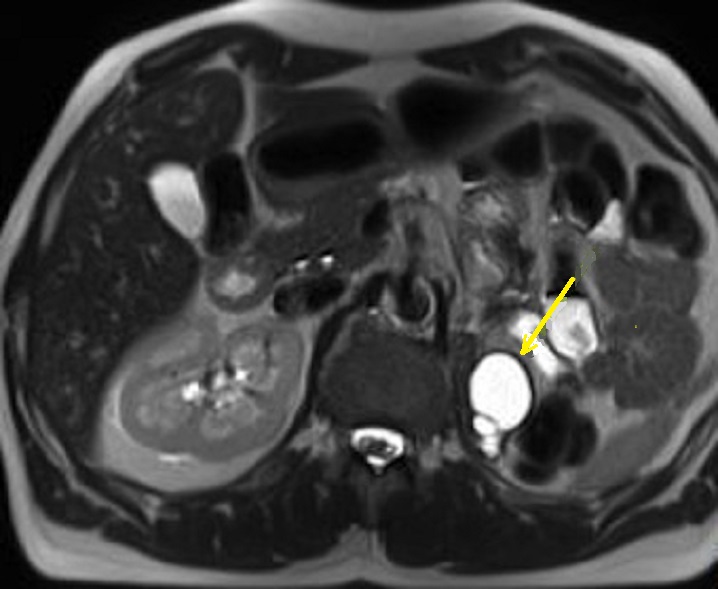

Meme cas en coupe IRM

axiale ponderation sur T2 . La contenue liquidienne

du kyste devient hypersignal ( fleche jaune ) situe

au queue du pancreas |